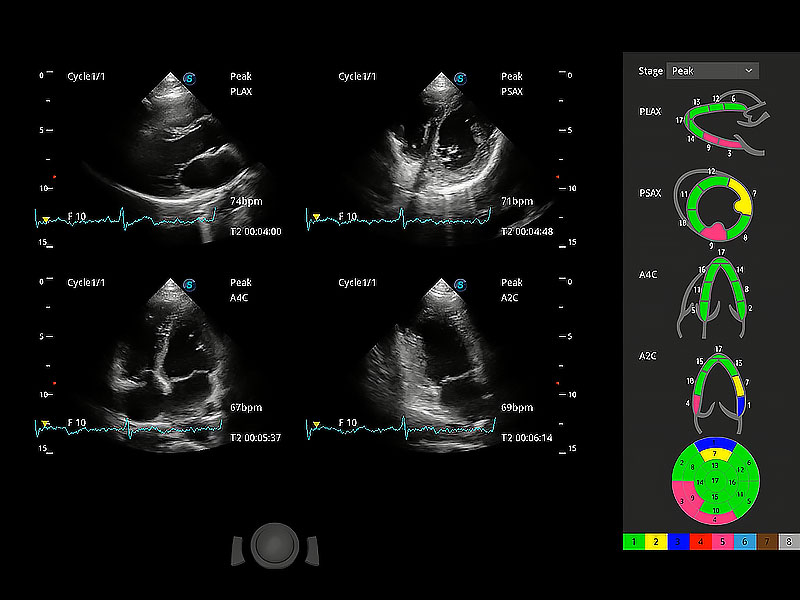

通過(guò)心肌識(shí)別技術(shù)與二維斑點(diǎn)追蹤技術(shù)相結(jié)合,對(duì)心臟的超聲圖像進(jìn)行量化分析。計(jì)算心肌17個(gè)節(jié)段的應(yīng)變、應(yīng)變率、速度、位移等,并通過(guò)牛眼圖的形式進(jìn)行呈現(xiàn)。

具備多種協(xié)議可選,同時(shí)支持17階段劃分法和專業(yè)的SE報(bào)告。